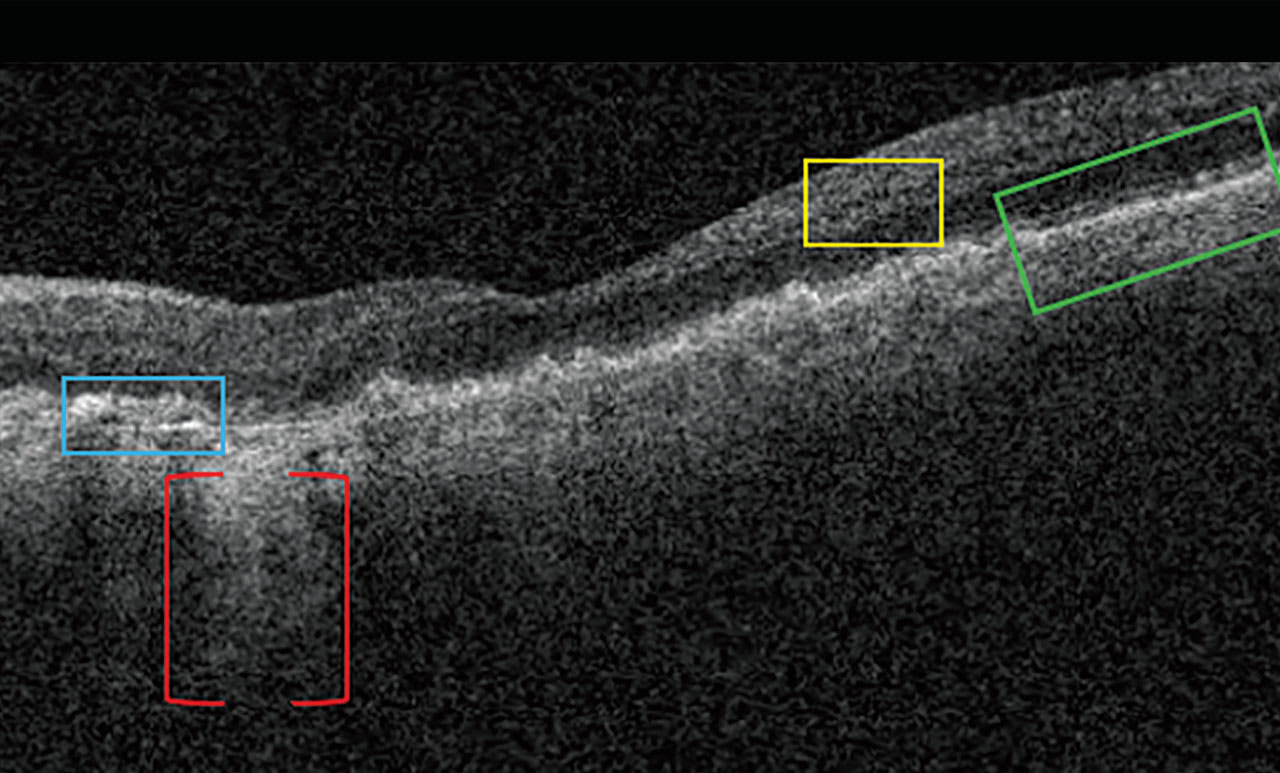

On OCT, drusen appear as RPE elevations. Calcified drusen have a hyporeflective core surrounded by a hyperreflective area on OCT (Figure 3). Patients who have heterogeneous internal reflectivity within drusen (HIRD) have a 6-fold risk of progressing to advanced AMD within a year.4

Reticular Pseudodrusen and Subretinal Drusenoid Deposits Reticular pseudodrusen (RPD), also called subretinal drusenoid deposits (SDD), are anterior to the RPE layer and have a reticular pattern of yellow-white lesions on CFP. RPD are associated with multifocal GA lesion development.1 On OCT (Figure 3), RPD are hyperreflective above the RPE (drusen are below the RPE). Patients who have RPD have a 2-fold increased risk of progressing to advanced AMD.5